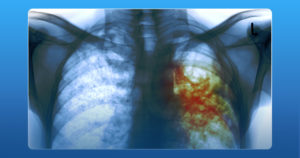

- Рентгенография.

При попадании возбудителя болезни в организм, в легких образуется малая гранулема. Здоровый организм с хорошим иммунитетом сам справляется с болезнью, гранулема заживает после симптомов, схожих с ОРВИ и переутомлением. Обнаружить зарубцевавшуюся гранулему можно только впоследствии – посредством рентгенологического исследования.

Под слабыми рентгеновскими лучами делают снимок грудной клетки. На нем отчетливо отражаются все туберкулезные гранулемы.

Рентгенография

Проводится для изучения имеющихся очагов поражения туберкулезом.